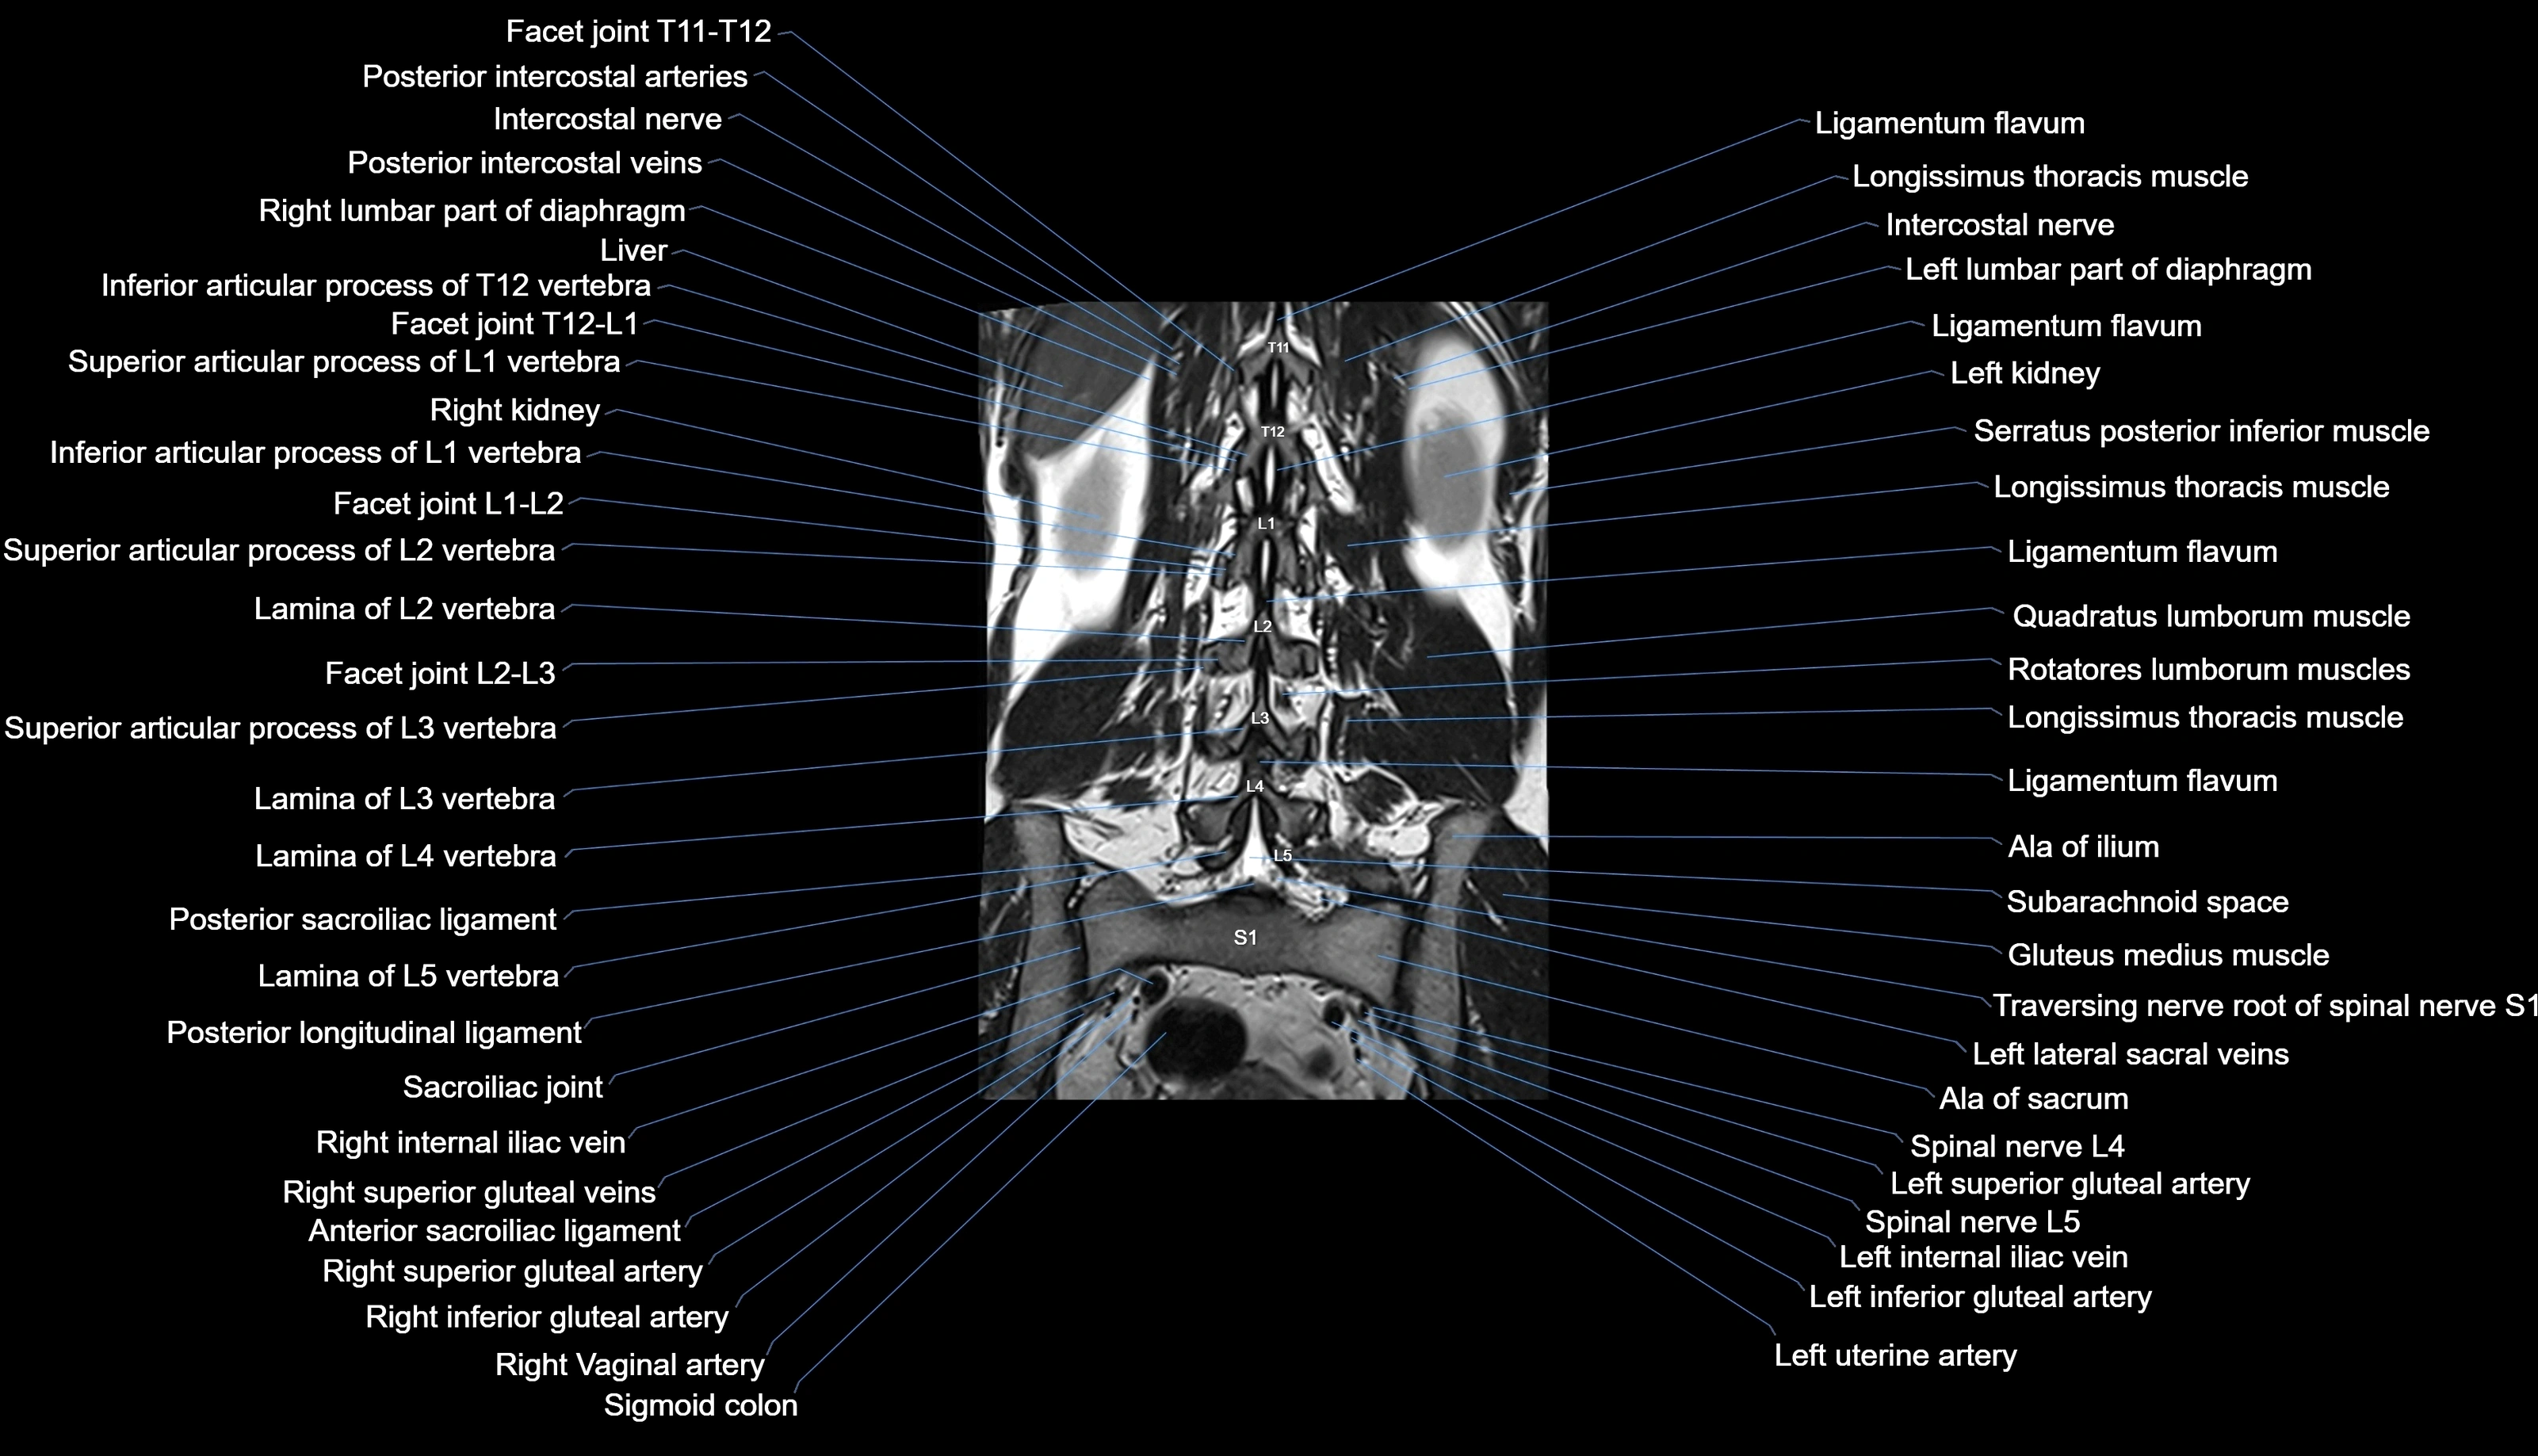

MRI images